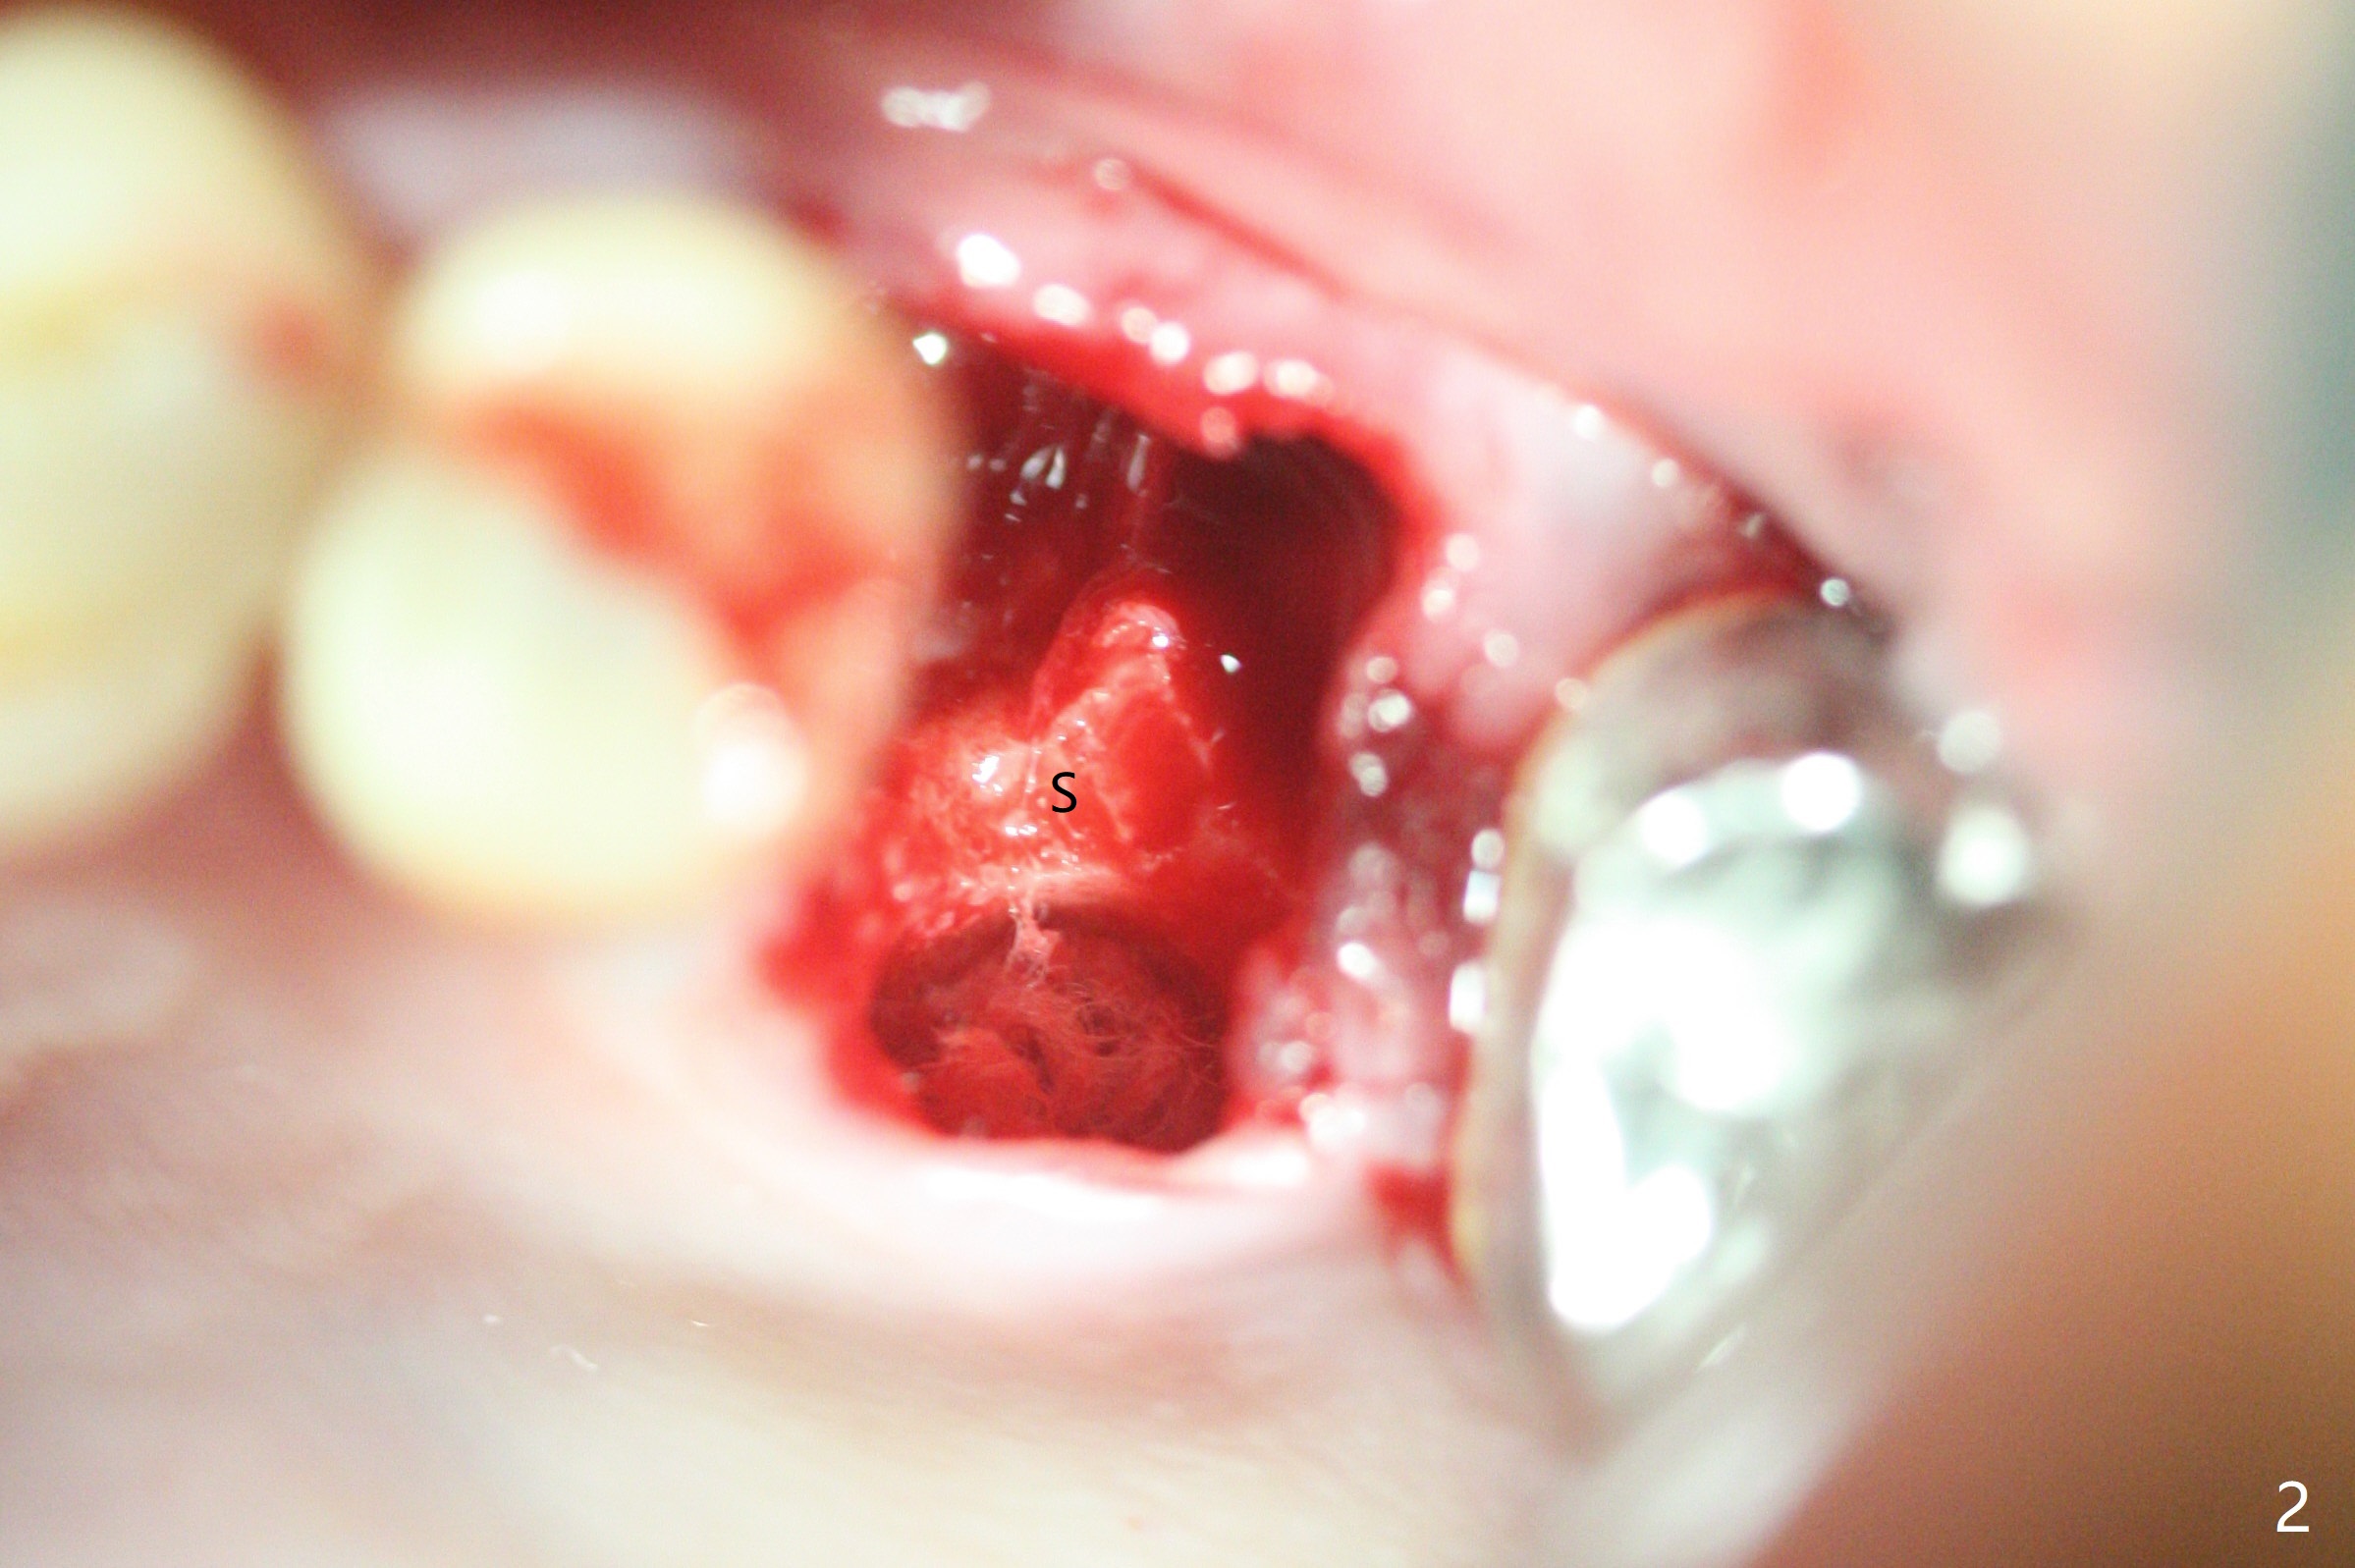

左上六拔除后,近中颊侧窝尤其大,与上颌窦相通(图一 *),而中隔比较尖,截除后还显得窄(图一,二:S),不太适合即刻种植。放置一块PRF膜于近中颊侧窝修补上颌窦,然后放置粘性骨块,好像有上颌窦提升迹象(图三:*(箭头:近中颊侧骨板缺失)),用骨粉填满其余牙槽窝(图四),覆盖另外一块PRF膜以及Cytoplast(不可吸收膜),用PTFE缝线(也不可吸收,与膜是同一个材料,非常柔软,好打结)缝合(图五)。最后使用牙周敷料。后者术后八九天脱落,病人术后十二天复诊,不可吸收膜腭侧有些外翻(图六箭头),伤口愈合尚可,没有骨粉丢失迹象,反复交代口腔卫生。再过三周撤除不可吸收膜。其实三周后膜自己脱落,病人回来撤去剩余缝线(图七),新鲜肉芽组织形成。术后5个月牙槽嵴和角化龈宽,骨高度尚可(图八),密度差些(图九,750单位),植体应该是4.5x8.5 或者 10 毫米,少量上颌窦提升。